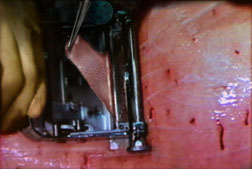

Staples

Staples are less reactive than the least reactive suture. Deeply implanted staples do not affect tissue defenses, although staple cross members that are flush with the skin can produce cross-hatched scarring. The development of disposable staplers with absorbable tacks obviates the need for removal of staples. Subcuticular closure of skin is now also possible through the use of a disposable stapler that uses twin gripper blades to approximate and evert the wound edges and insert a disposable pin into the dermis